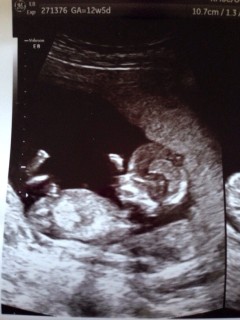

写真には12w2dと書いてありますが、予定日からの計算では12w5dです。 サイズは56.26ミリ。